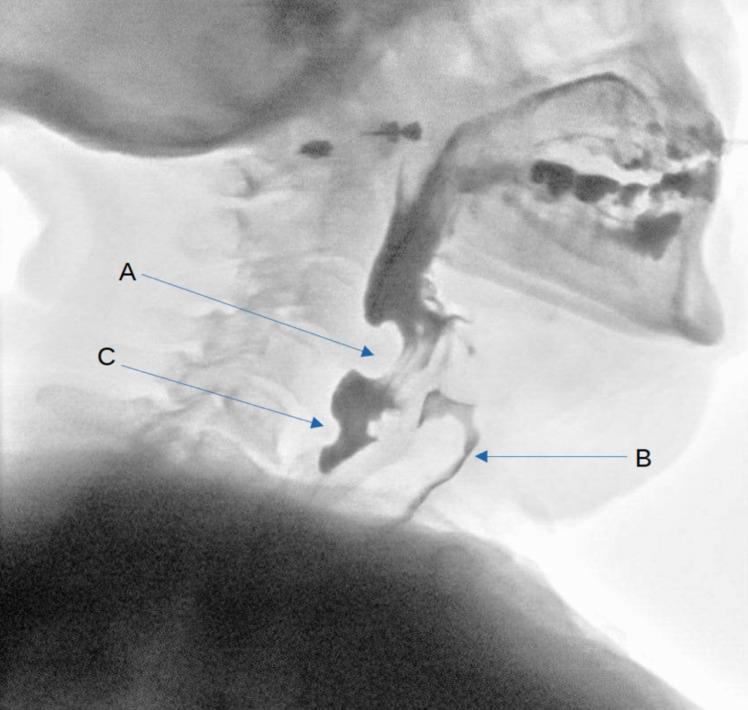

异常颈内动脉导致的吞咽困难:一例报告

Dysphagia from an aberrant internal carotid artery: a case report.

We present a case of dysphagia caused by an aberrant internal carotid artery (ICA). By reporting this rare occurrence, we hope to highlight the anomaly as a differential in cases of persistent, progressive dysphagia.

我们报告一例由异常颈内动脉(ICA)引起的吞咽困难病例。通过报告这一罕见病例,我们希望强调该异常情况可作为持续性、进行性吞咽困难病例的鉴别诊断之一。